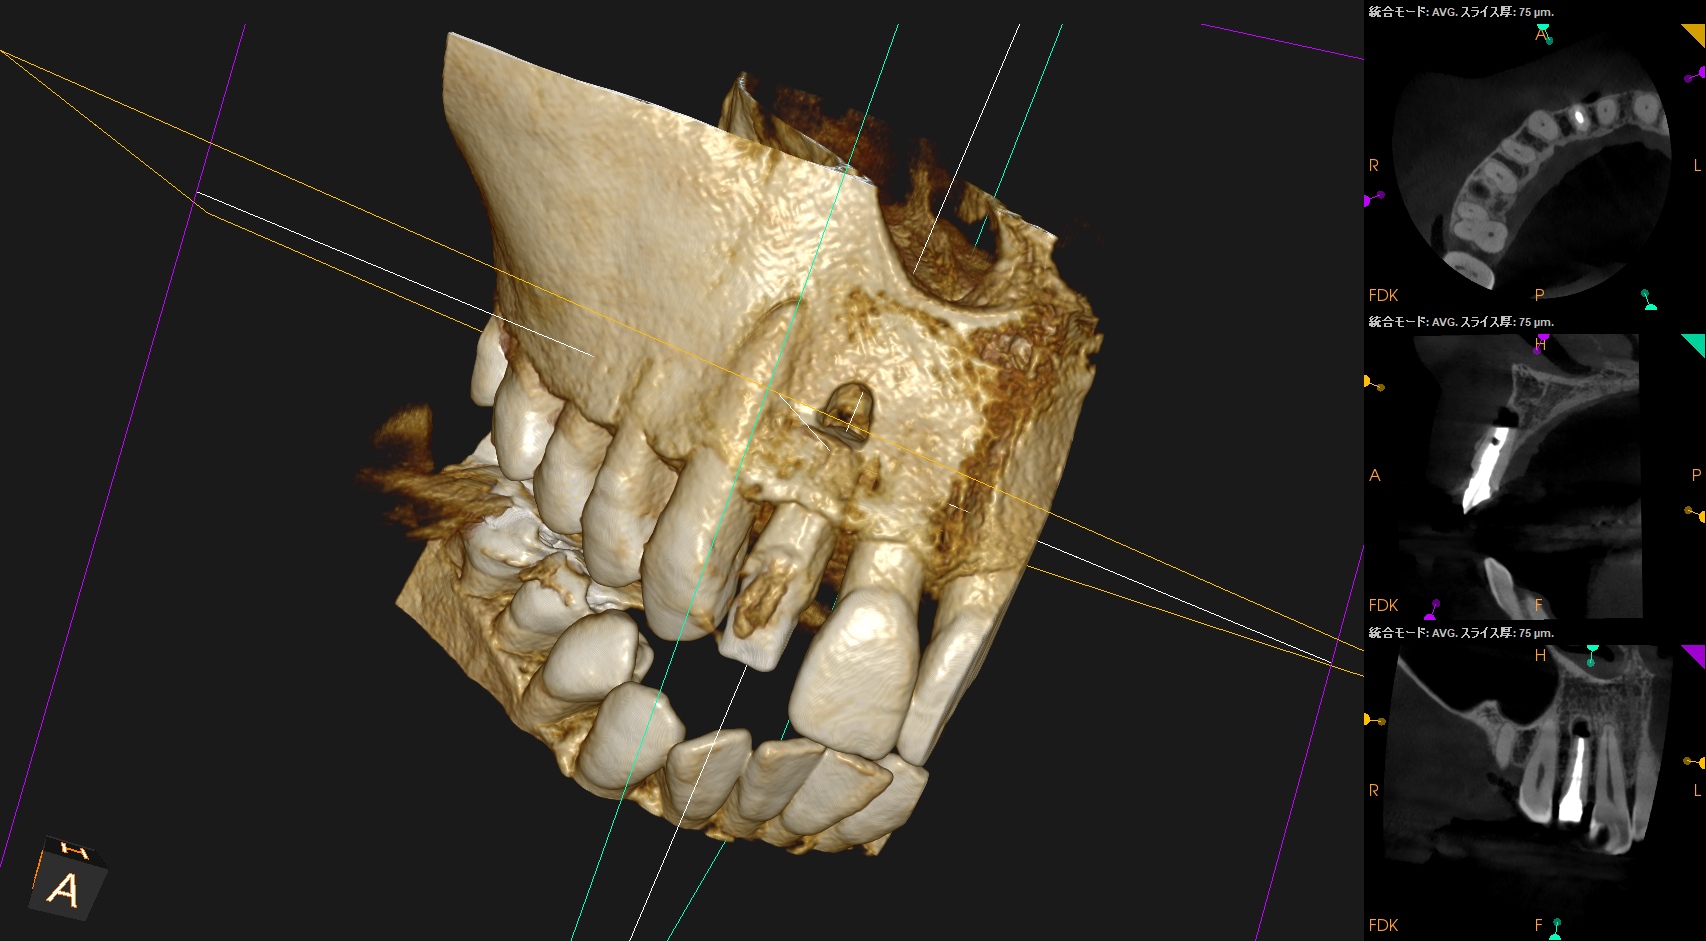

根尖が既に開いており、圧痛があったことから治療は再根管治療ではなく、歯根端切除術であるということがわかる。

クラウンのマージンより11.5mm下方に#7のApexはあり、そこを3mm切断するには頬舌的に4.4mmの幅があるということがわかる。

実にEasyなApicoectomyだ。

Recommended Tx: Core build up w Fiber Post⇨Apicoectomy

術後にPA, CBCTを撮影した。

気泡が逆根管充填材に混入したが、問題はないだろう。

初診時と比較した。

気泡は入ったが劇的に治癒し、臨床症状もないことからこの日で終診となった。